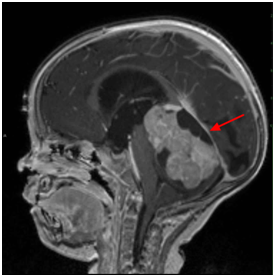

髓母细胞瘤 是位于小脑的脑肿瘤,小脑是控制平衡,协调和其他复杂运动功能的大脑部分。髓母细胞瘤较常生长在小脑的中央部位,而在小脑的外部部分则...

髓母细胞瘤 是儿童中较常见的恶性脑肿瘤。根据定义,髓母细胞瘤发生在小脑中,小脑是位于头骨基部的脑部的一部分,位于脑干上方。小脑参与许多功能...

髓母细胞瘤 是一种癌性脑肿瘤。它在小脑中发育,小脑是头骨底部附近的大脑的一部分。髓母细胞瘤可以扩散到中枢神经系统 (大脑和脊髓)。儿童大多...

髓母细胞瘤,这种起源与胚胎残余细胞的肿瘤可发生在脑组织的任何部位,但多数生长在四脑室顶之上的小脑蚓部,是中枢神经系统恶性程度较高的肿瘤之...

髓母细胞瘤(MB,medulloblastoma)呈双峰发病,高发年龄段一个在4~8岁之间,另一个在21~40岁之间;MB为富血供、富细胞肿瘤(另一个富细胞肿瘤为CNS淋巴瘤)...

髓母细胞瘤是后颅窝比较常见的恶性肿瘤,也是中枢神经系统恶性程度较高的神经上皮性肿瘤之一。它的细胞形态很像胚胎时期的髓母细胞,因此得名。髓母...